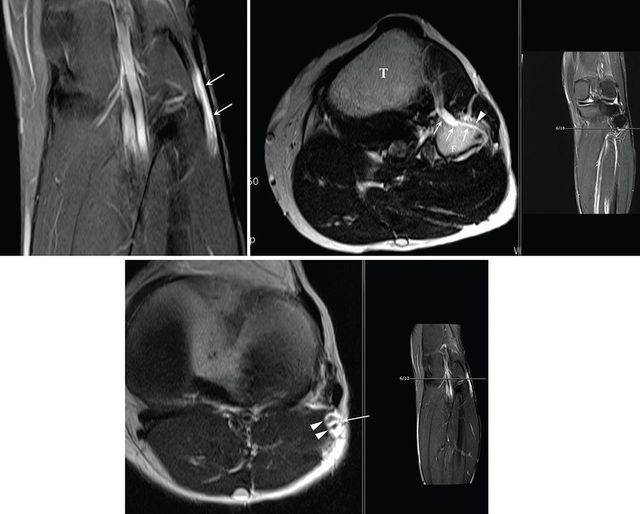

가톨릭대학교 서울성모병원 신경외과 손병철 교수는 최근 미국 메이요 클리닉(Mayo Clinic) 신경외과 로버트 스피너(Robert J. Spinner) 교수팀과의 공동 연구를 통해 말초신경 마비를 유발하는 신경내 결절종(intraneural ganglion cyst)의 복잡한 발생 기전을 명확히 규명하였다. 신경내 결절종은 관절 내부의 활액이 신경 지배 분지를 타고 역류하여 신경 줄기 내부에 낭종을 형성하는 질환으로, 과거에는 원인이 불분명하여 수술 후에도 재발이 잦고 영구적인 신경 손상을 남기는 난치성 질환으로 분류되었다.

이번 성과는 지난 2018년 국제 학술지 ‘Asian Journal of Neurosurgery’에 발표한 손 교수의 증례 보고인 ‘비골신경 마비를 유발하는 신경곁조직 아래막 결절종’ 에서부터 시작되었다. 당시 손 교수는 2016년 메이요 클리닉 연구팀이 최초 확인하여 학계에 보고한 ‘신경곁조직 아래막(subparaneurial)’ 결절종이라는 매우 희귀한 변이를 실제 임상 현장에서 발견하고, 이를 성공적으로 치료한 과정을 상세히 기술하였다. 이는 기존에 알려진 신경외막(epineurium) 내부의 결절종과는 달리, 신경을 감싸는 더 깊은 층인 신경곁조직 아래 공간을 따라 낭종이 확산되는 독특한 병태생리를 규명한 중요한 전환점이 되었다.

특히 손 교수는 해당 연구를 통해 신경곁조직 아래막 결절종이 일반적인 결절종보다 신경 섬유에 더 밀착되어 있으며, 신경 줄기를 따라 매우 광범위하고 빠르게 전이될 수 있다는 사실을 확인하였다. 이러한 특성 때문에 일반적인 낭종 제거술로는 완치가 어려운 만큼, 관절과 연결된 신경 분지를 근본적으로 차단하는 정교한 수술 기법 적용이 필요할 수 있음을 제시하였다.

이후 손 교수는 지난 8년간 비골신경, 척골신경, 요천추신경총, 궁둥신경 등 인체 전반의 말초신경에서 발생하는 증례들을 지속적으로 추적하며 임상 데이터를 축적해 왔다. 2025년 메이요 클리닉과의 공동 연구 과정에서 이러한 데이터는 연구의 완성도를 높이는데 기여한 것으로 알려졌다. 연구팀은 신경곁조직 아래막 결절종이 신경의 주 경로뿐만 아니라 해부학적으로 분리된 여러 신경 분지로까지 확산될 수 있다는 병태생리 파트 1, 2 논문을 완성하였다. 이는 활액이 이동하는 미세한 해부학적 통로를 완벽히 이해해야만 재발 없는 치료가 가능하다는 사실을 과학적으로 입증한 것이다.